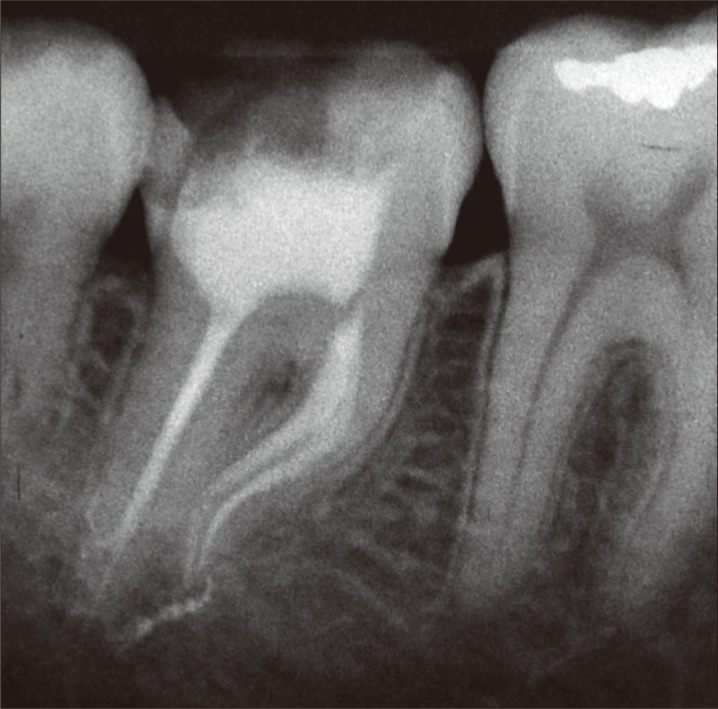

Biomechanical preparation of the cervical and middle thirds was performed using the Reciproc system (VDW GmbH, Munich, Germany) coupled to the electric motor Silver Reciproc VDW handpiece (Sirona Dental Systems GmbH, Bensheim, Germany) with 6 : 1 reduction in the Reciproc ALL mode and a R25 file with 0.08 taper. When the cervical and middle thirds were finalized, the working length was measured with the aid of an electronic apex locator (Joypex 5, Denjoy Dental Co., Ltd., Changsha, China), which revealed that the real working length was 20 mm in the mesio-buccal and mesio-lingual canals, and 22 mm in the distal canal. To finalize and refine apical preparation, the R25 file of the Reciproc system was used again in the real working length. At each change of instrument, the canals were irrigated with 2.5 mL of 2.5% Sodium Hypochlorite solution (Biodinâmica, Ibiporã, PR, Brazil) using a disposable syringe and NaviTip needle (Ultradent, South Jordan, UT, USA). After complete instrumentation, 17% ethylenediaminetetraacetic acid (EDTA, Biodinâmica, Ibiporã, PR, Brasil) was used for smear layer removal. The canals were dried with absorbent paper points R5 (VDW GmbH) and filled using gutta-percha cones R25 (VDW GmbH) and AH Plus sealer (Dentsply Maillefer), by thermal compaction technique using McSpadden #50 (Dentsply Maillefer).

Next, the pulp chamber was cleaned to remove the excess of gutta-percha and sealer. Glass-ionomer restorative cement (Vidrion R, SS White, Rio de Janeiro, RJ, Brazil) was used as temporary restoration due to its good sealing ability and fluoride release. After 2 weeks, the tooth was definitely restored with composite resin (Z250, 3M ESPE, Sumaré, SP, Brazil) (Figure 2). Continued follow-up over 6 months has shown a successful outcome from endodontic perspective (Figure 3). Clinically, the tooth presented no painful symptomatology, and radiographically, no signs of failure in root canal filling or periapical lesions were observed.